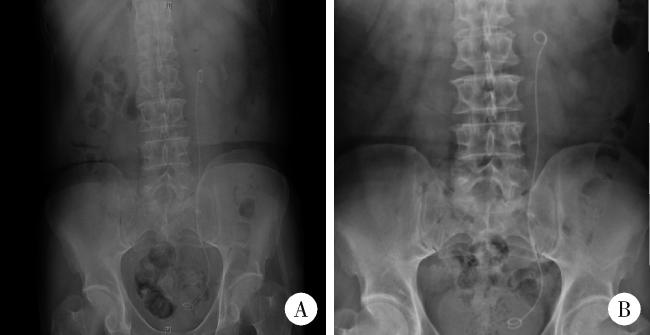

图1 最大径≥1.5 cm输尿管结石的术前影像学表现Figure 1 Imaging characteristics of urolithiasis with largest diameter ≥ 1.5 cm A, coronal CT image, with the arrow indicating the left ureteral calculus, measuring greater than 1.5 cm in length; B, axial CT image, where the arrow marks the location of the calculus; C, sagittal CT image, with the arrow identifying the calculus; notable hydronephrosis due to ureteral obstruction is observed above the calculus (indicated by the triangle); D, the kidneys, ureters, and bladders appearance of a ureteral calculus with a maximum dia-meter of ≥1.5 cm, highlighted by the arrow. |